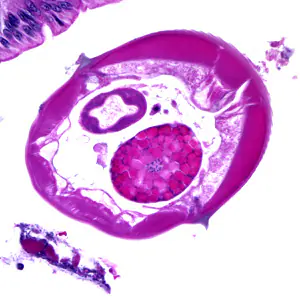

Case #174 – February, 2006

A teenager underwent surgery for a traumatic injury to his abdominal cavity. Apart from the injury, the surgeon noticed some necrosis around the youth’s appendix. A biopsy of that area was obtained and sent to the pathology department. Figures A-D show what was observed on one of the hematoxylin and eosin (H & E) stained slides of tissue section. Figures A, B and D were taken at 200×, and Figure C was taken at 400× magnification, respectively. What is your identification of this additional finding? Based on what criteria?

Figure A

Figure B

Figure C

Figure D